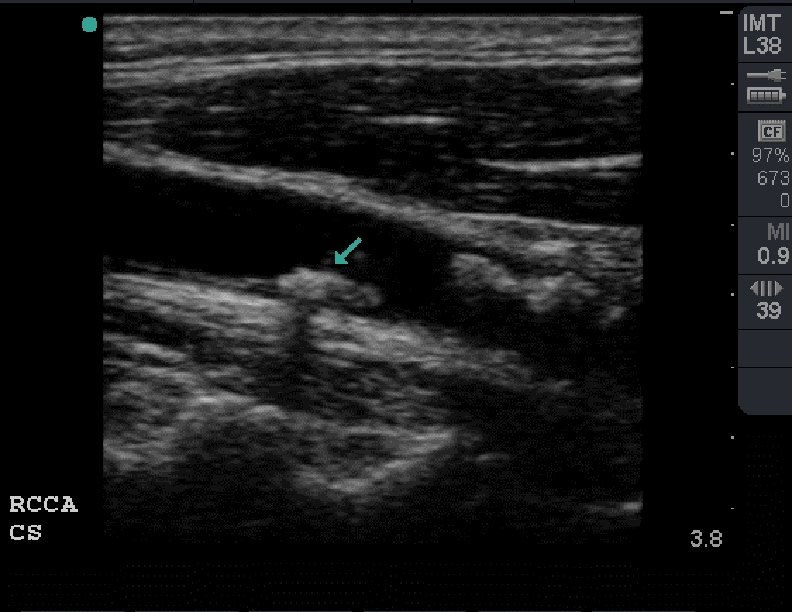

Heterogeneous Plaque

Heterogeneous Plaque Longitudinal view